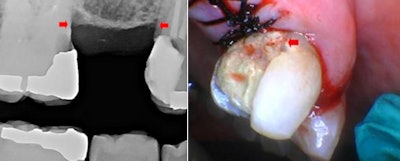

This case involved a healthy 73-year-old woman and her general dentist. She was deciding between two clinical treatments: an implant to replace tooth #4 or a fixed partial denture from teeth #3 and #5 with pontic #4. The patient was encouraged to obtain an implant instead of a fixed partial denture (bridge) because of longevity, especially with her caries susceptibility. Figure 1 shows the site with bone level indicated by red arrows.

There was inadequate tooth structure for restorations at #3 mesial and #5 distal because of decay near the crest of the alveolus.

For the progression of this case in the photos, a red arrow is used in the distobuccal of tooth #5 to denote a reference point relative to tissue level.